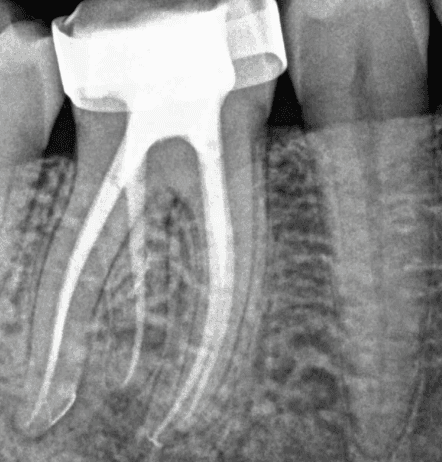

Dr Kreena Patel understands the importance of preserving tooth tissue for the long-term health and strength of your tooth. She uses conservative access and modern instrumentation techniques, including rotary files and microscopic guidance, to treat the tooth precisely and minimally invasively.

KREENA'S CASES